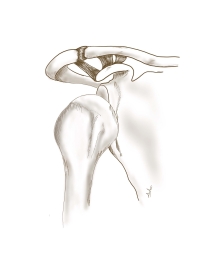

Εικόνα 2. Η Χειρουργική αποκατάσταση αφορά τη συρραφή του τένοντα και τη χρήση νάρθηκα ιπποποδίας. Ο ίδιος νάρθηκας χρησιμοποιείται στις περιπτώσεις συντηρητικής θεραπείας.